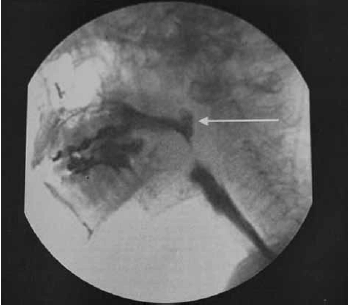

A imagem a seguir refere-se a um videodeglutograma de um paciente com traumatismo cranioencefálico.

(JOTZ. Tratado de deglutição e disfagia. 2018. p. 271)

Assinale a alternativa que apresenta um diagnóstico compatível com a imagem.